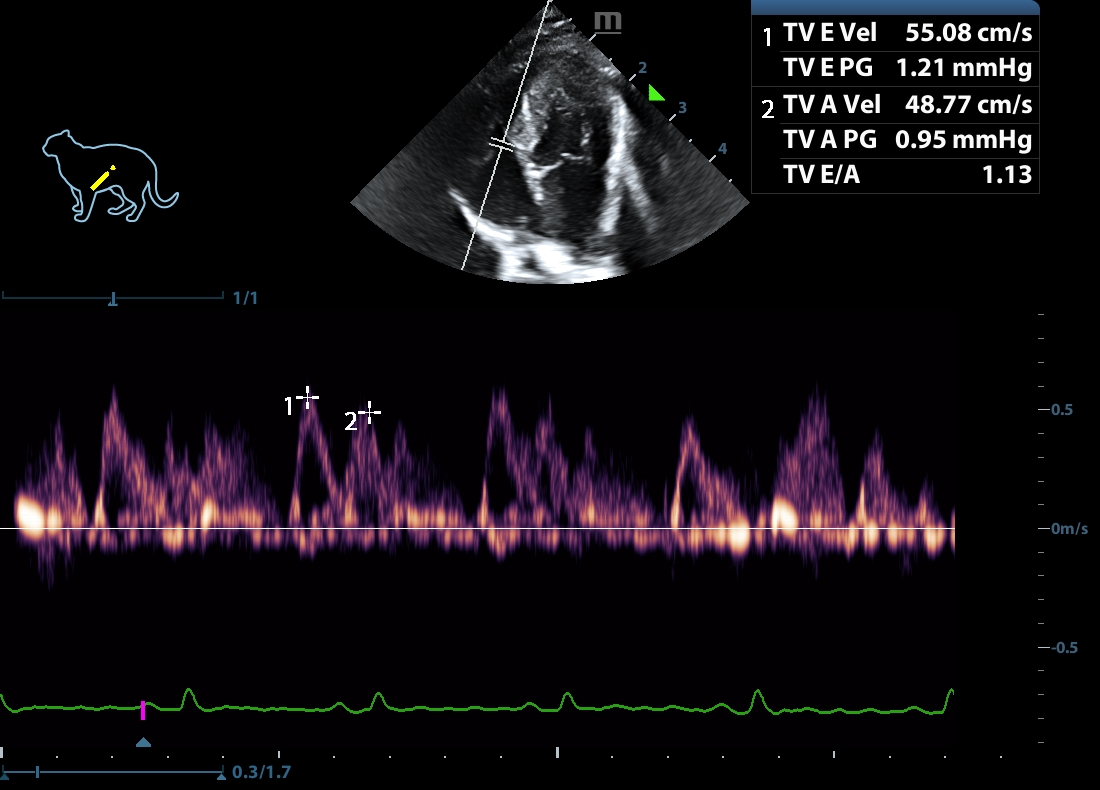

202505170048360153CARD.JPG